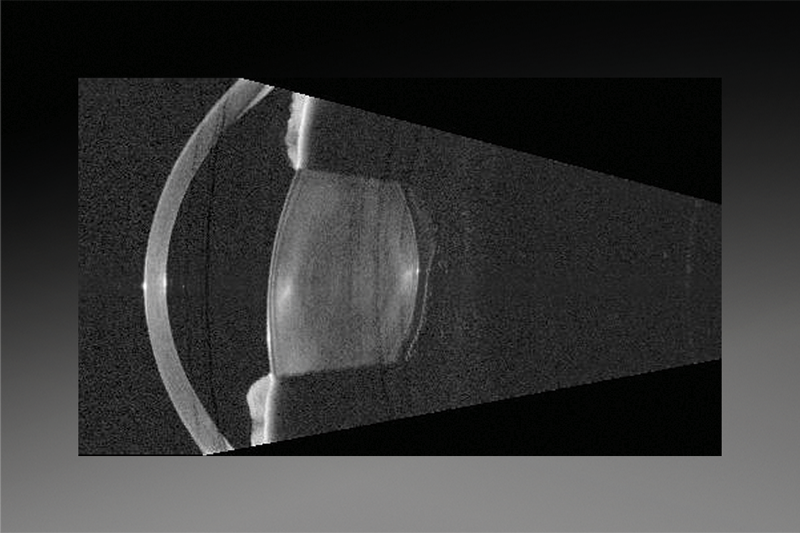

ОКТ-зображення передньої камери з поправкою на рефракцію та B-сканування дозволяє візуально оцінити анатомію у 16 поперечних перерізах. Крім того, програмне забезпечення також визначає тривимірну орієнтацію та розташування лінзи і відображає відповідну інформацію на інтуїтивно зрозумілому екрані докладних результатів із зображенням поперечного перерізу B-сканування у напрямку максимального нахилу лінзи.